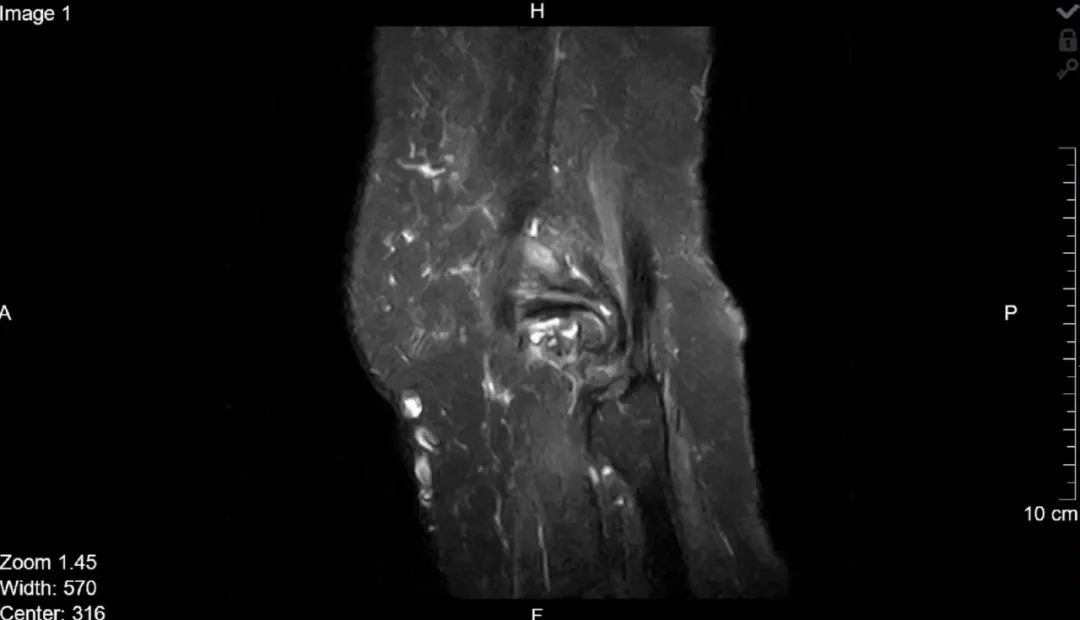

对于人体中的核磁共振成像,通常以氢核为目标,因为其中水和脂肪中有很多,然后图像的亮度基本上可以告诉我们脂肪和水的数量。人们也可以瞄准其它原子核并进行测量,这就导致了不同核磁共振图像的工作方式不同。核磁共振成像非常适合于检查软组织,而对于骨折一般则使用X射线成像。

上述提到,共振频率与磁场强度成正比,正因为如此,我们可以使用磁场梯度来瞄准特定位置的原子核,生成不同位置的身体切片图像。